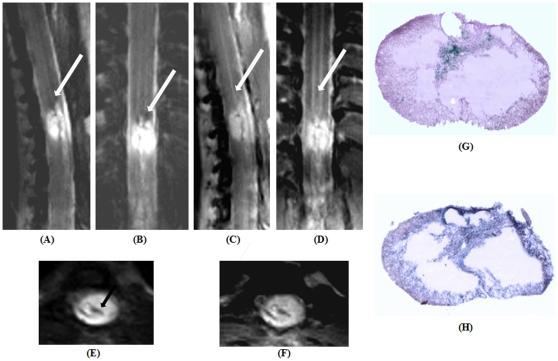

This study attempts to configure and optimize a clinical 3 Tesla magnetic resonance scanner to facilitate imaging of small animal central nervous system pathologies. The hardware of the scanner was complemented by a custom-built, 4-channel phased array coil system. Extensive modification of standard sequence protocols was carried out based on tissue relaxometric calculations. Proton density differences between the gray and white matter of the rodent spinal cord along with transverse relaxation due to magnetic susceptibility differences at the cortex and striatum of both rats and mice demonstrated statistically significant differences. The employed parallel imaging reconstruction algorithms had distinct properties dependent on the sequence type and in the presence of the contrast agent. The attempt to morphologically phenotype a normal healthy rat brain in multiple planes delineated a number of anatomical regions, and all the clinically relevant sequels following acute cerebral ischemia could be adequately characterized. Changes in blood-brain-barrier permeability following ischemia-reperfusion were also apparent at a later time. Typical characteristics of intra-cerebral haemorrhage at acute and chronic stages were also visualized up to one month. Two models of rodent spinal cord injury were adequately characterized and closely mimicked the results of histological studies. In the employed rodent animal handling system a mouse model of glioblastoma was also studied with unequivocal results.

本研究试图配置和优化临床 3 特斯拉磁共振扫描仪,以方便对小动物中枢神经系统病变进行成像。扫描仪的硬件由定制的 4 通道相控阵线圈系统补充。根据组织弛豫计算,对标准序列协议进行了广泛的修改。在大鼠和小鼠的皮质和纹状体中,由于磁化率差异导致的横向弛豫,对啮齿动物脊髓的灰质和白质之间的质子密度差异进行了广泛的测量,结果显示存在统计学上的显著差异。所采用的并行成像重建算法具有依赖于序列类型和存在对比剂的不同特性。试图在多个平面上对正常健康大鼠的大脑进行形态表型分析,描绘了许多解剖区域,并且可以充分描述所有与临床相关的急性脑缺血后的后续情况。缺血再灌注后血脑屏障通透性的变化在稍后时间也变得明显。在急性和慢性阶段的颅内出血的典型特征也可以在一个月内进行可视化。两种啮齿动物脊髓损伤模型也得到了充分的描述,并与组织学研究的结果非常相似。在采用的啮齿动物处理系统中,还对胶质母细胞瘤的小鼠模型进行了研究,结果明确。